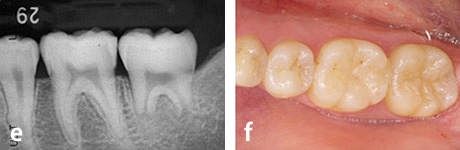

e、f : 移植後6ヶ月

g、h : 移植後3年